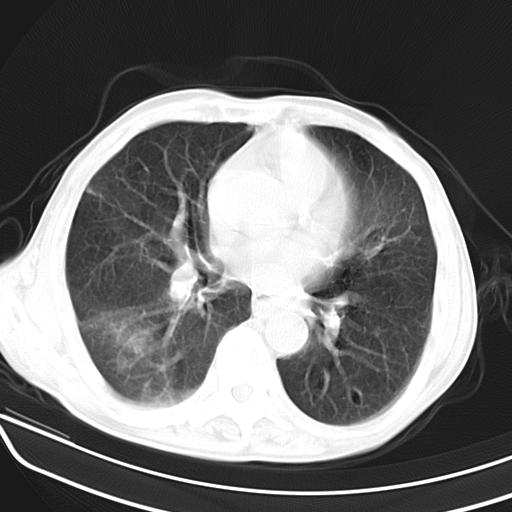

男,70,发烧咳嗽咳痰10余天,查痰结核菌阴性。否认以前有肺病史。治疗10天后症状减轻。 img]/upload/forum/2009/12/302117469692.jpg[/img]

双肺多发斑片状条索样及网格状改变,右上肺可见大个空洞,首先考虑tb慢性炎症并空洞形成。

双肺多发斑片状条索样及网格状改变,右上肺可见大个空洞,首先考虑tb慢性炎症并空洞形成。特发行纤维化。肺癌待排。

影像所见:右上肺见一巨大厚壁空洞,内壁欠光整,右上肺广泛斑片状、大片状模糊阴影。

影像所见:右上肺见一巨大厚壁空洞,并见分隔,内壁欠光整,右上肺广泛斑片状、大片状磨玻璃阴影。